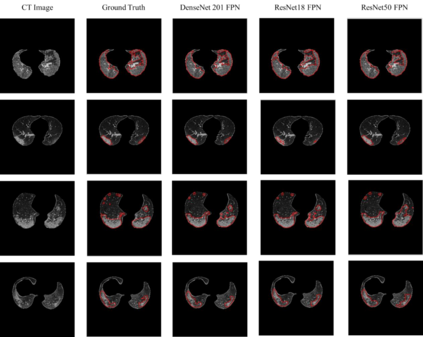

Since the breakout of coronavirus disease (COVID-19), the computer-aided diagnosis has become a necessity to prevent the spread of the virus. Detecting COVID-19 at an early stage is essential to reduce the mortality risk of the patients. In this study, a cascaded system is proposed to segment the lung, detect, localize, and quantify COVID-19 infections from computed tomography (CT) images Furthermore, the system classifies the severity of COVID-19 as mild, moderate, severe, or critical based on the percentage of infected lungs. An extensive set of experiments were performed using state-of-the-art deep Encoder-Decoder Convolutional Neural Networks (ED-CNNs), UNet, and Feature Pyramid Network (FPN), with different backbone (encoder) structures using the variants of DenseNet and ResNet. The conducted experiments showed the best performance for lung region segmentation with Dice Similarity Coefficient (DSC) of 97.19% and Intersection over Union (IoU) of 95.10% using U-Net model with the DenseNet 161 encoder. Furthermore, the proposed system achieved an elegant performance for COVID-19 infection segmentation with a DSC of 94.13% and IoU of 91.85% using the FPN model with the DenseNet201 encoder. The achieved performance is significantly superior to previous methods for COVID-19 lesion localization. Besides, the proposed system can reliably localize infection of various shapes and sizes, especially small infection regions, which are rarely considered in recent studies. Moreover, the proposed system achieved high COVID-19 detection performance with 99.64% sensitivity and 98.72% specificity. Finally, the system was able to discriminate between different severity levels of COVID-19 infection over a dataset of 1,110 subjects with sensitivity values of 98.3%, 71.2%, 77.8%, and 100% for mild, moderate, severe, and critical infections, respectively.